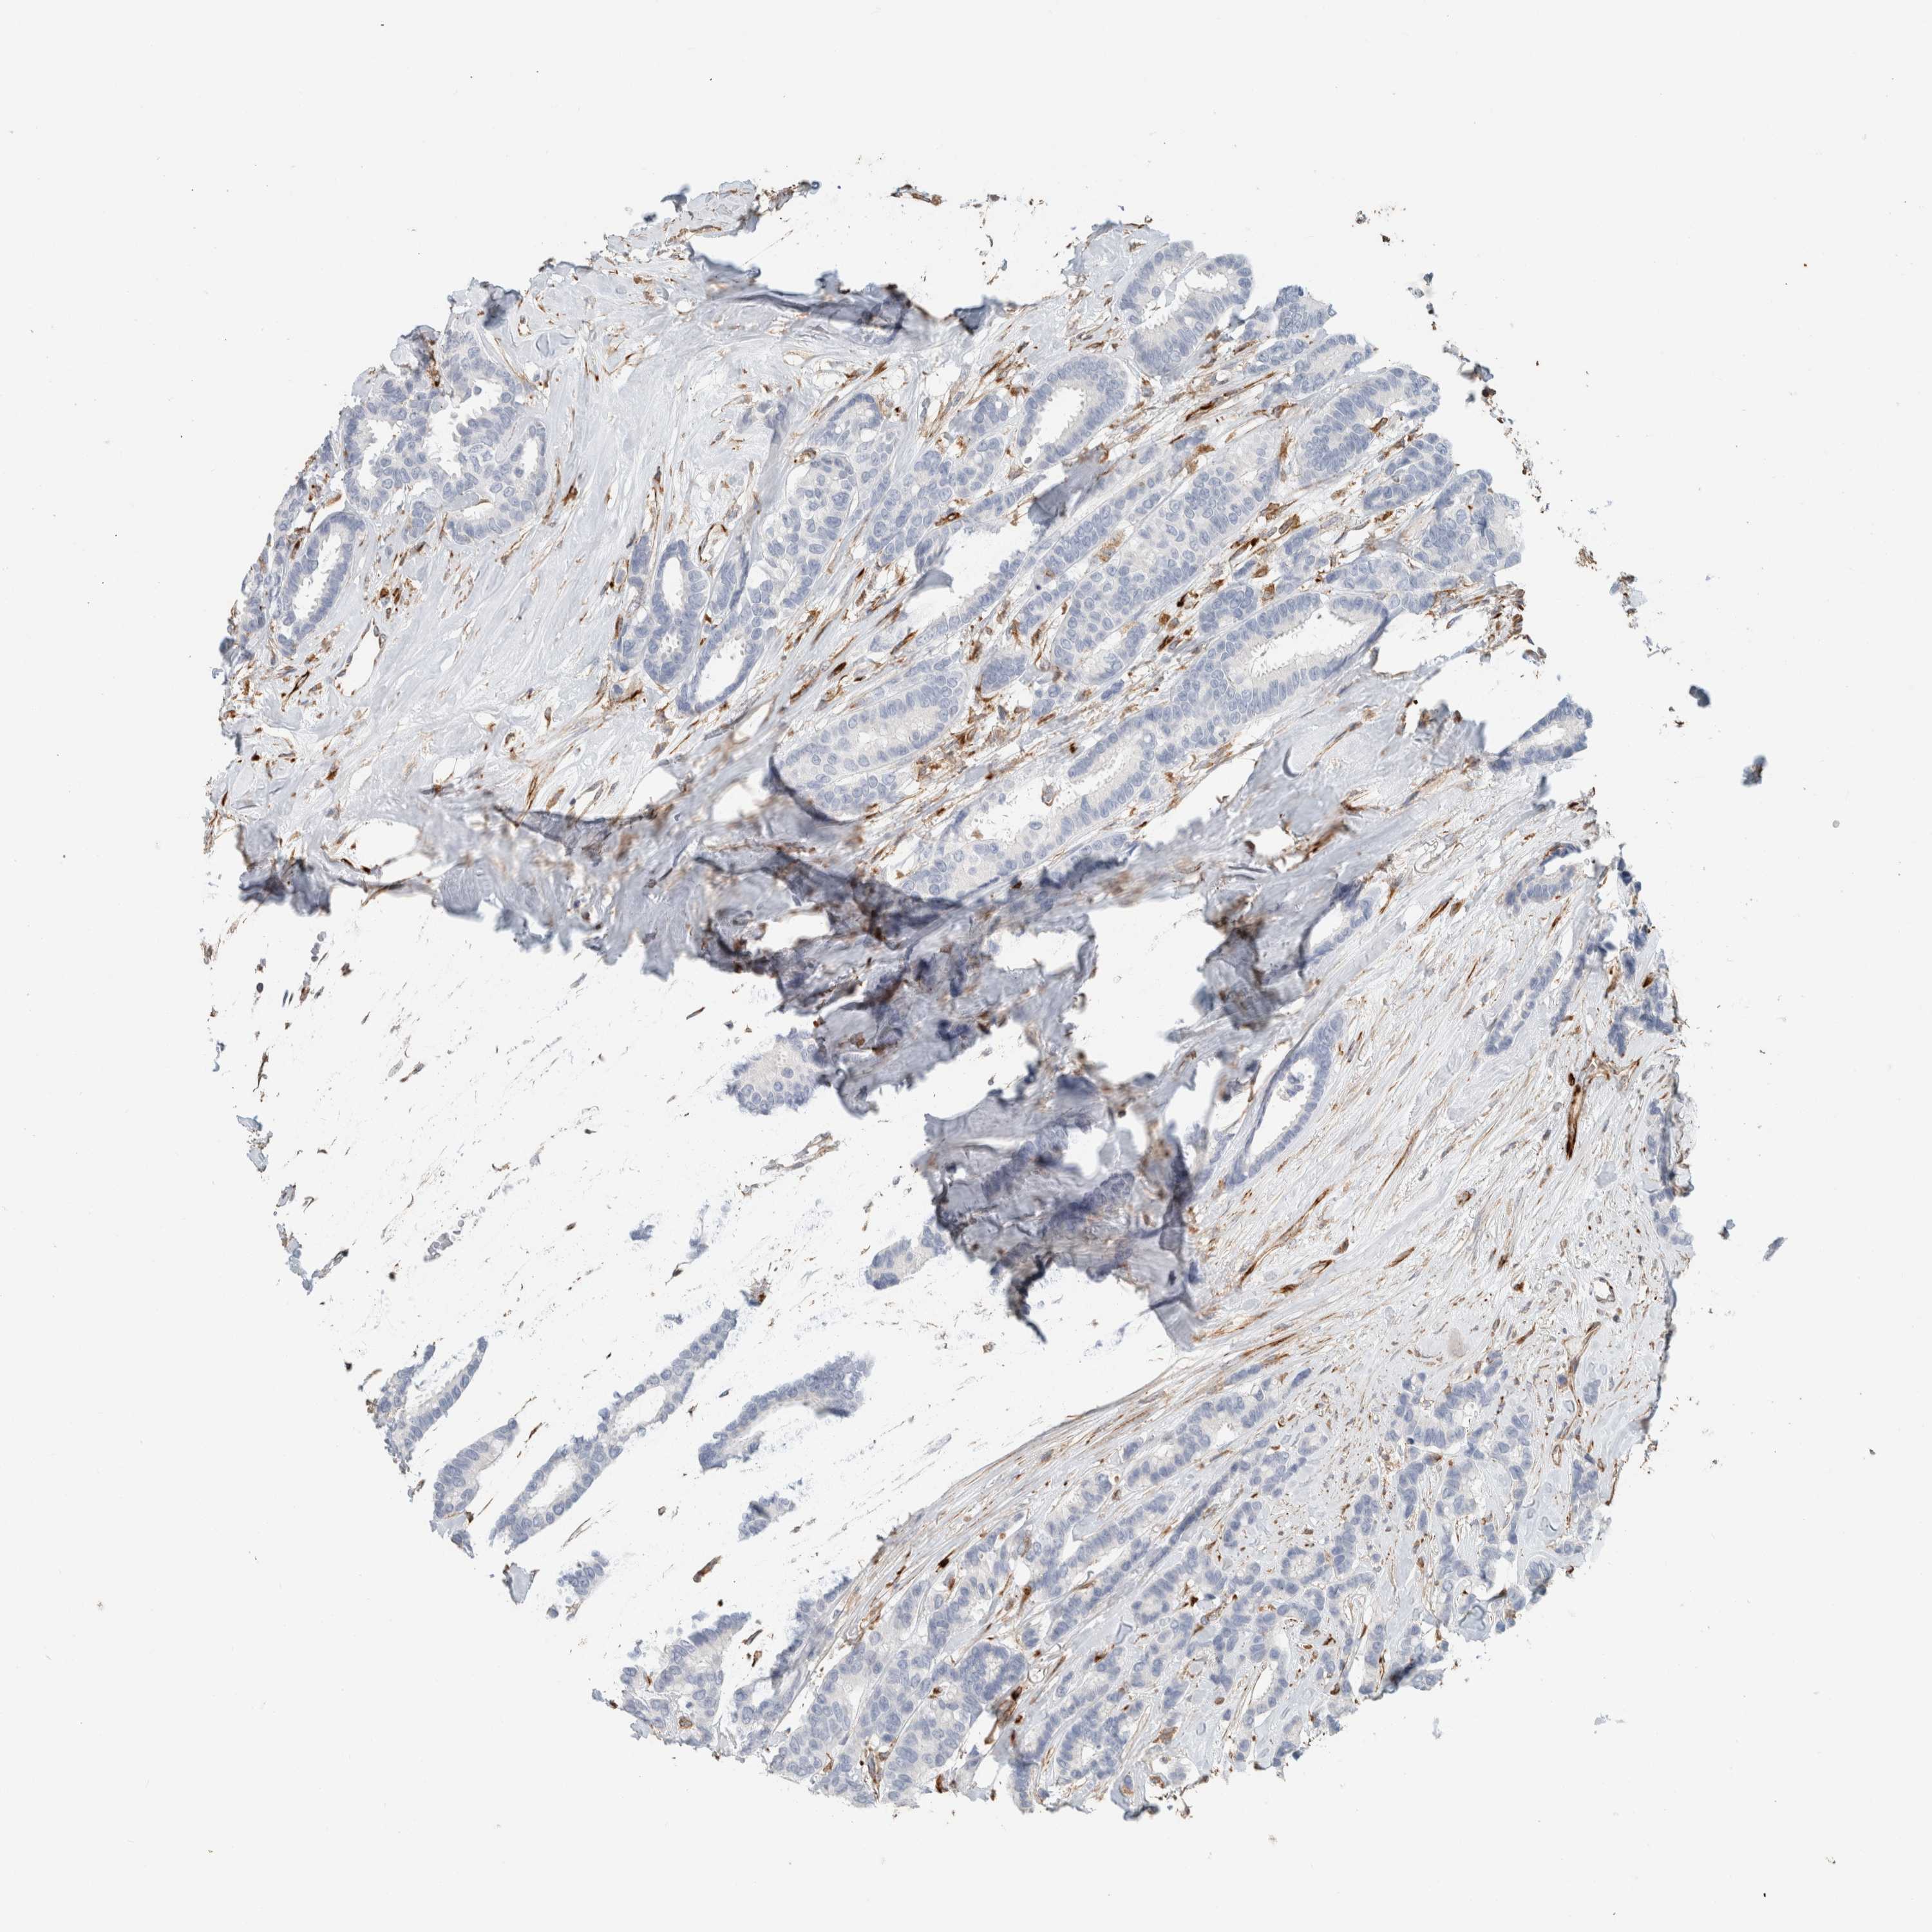

CANCER BREAST CANCER Show tissue menu

BRCA TCGA BRCA VALIDATION PROTEIN EXPRESSION